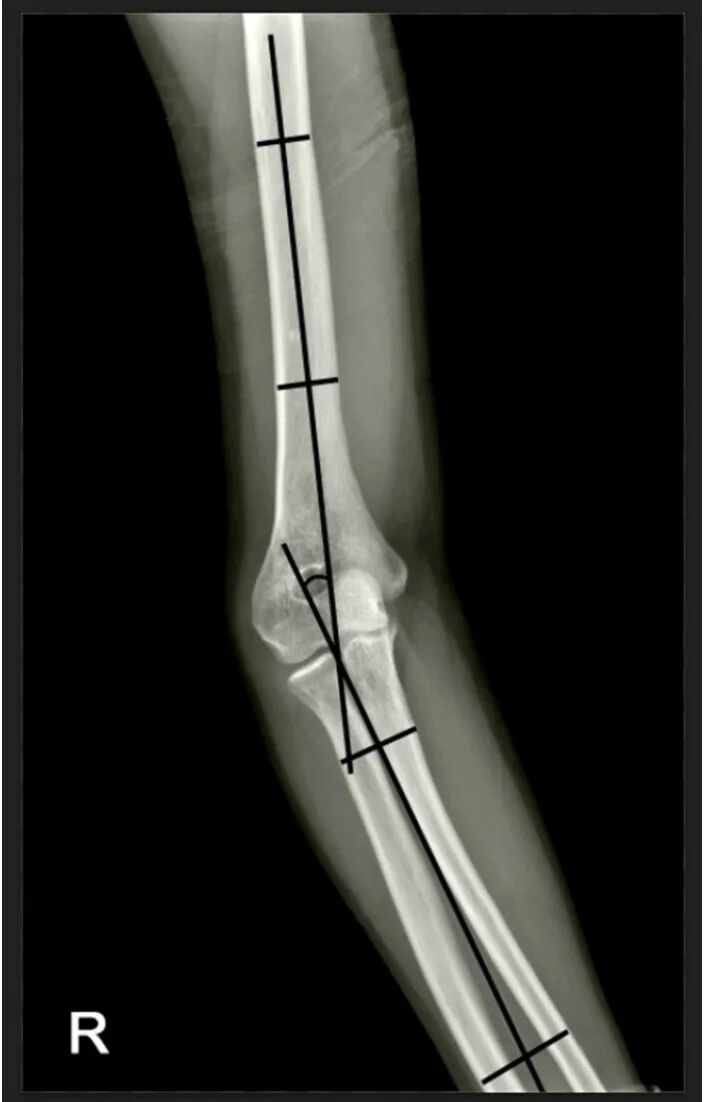

• 在进行X线检查时,评估双上肢(患侧和健侧)的携带角和鲍曼角carrying angle and Baumann angle。计划截骨术切除的角度应大致等于患侧携带角与健侧携带角之差。需要注意的是,应仔细评估肘关节前后位X线片(拍摄时,前臂完全旋后,垂直于中立位肘关节拍摄);肱骨远端的屈曲或伸展畸形可能会改变X线携带角,应予以考虑

使用肘关节前后位 X 光片,在冠状面上规划截骨术,以准确矫正内翻,并尽量减少侧向突出。

• 使用前后位 X 光片,通过从未受影响的手臂的携带角中减去受影响手臂的携带角来计算矫正角 (AOC)

• 以AOC作为两条线之间的夹角,画一个V形。这两条线将分别代表近端(P)和远端(D)截骨切口。

• 将V形尖端沿肱骨远端内侧皮质放置,略高于内上髁。然后沿肱骨远端内侧皮质向上或向下滑动尖端,直至(1)远端切口略高于鹰嘴窝,且(2)近端切口长度大于或等于远端切口长度(图1)

• 为了验证侧向突出是否最小,请确保远端切口与病理关节线倾斜

图 1

图 1. 截骨部位初始模板。本例中矫正角度 (AOC) 为 25°。下方以虚线标示病变关节面。P = 近端截骨,D = 远端截骨,d = 克氏针之间的距离,表示截骨切口的侧入路。